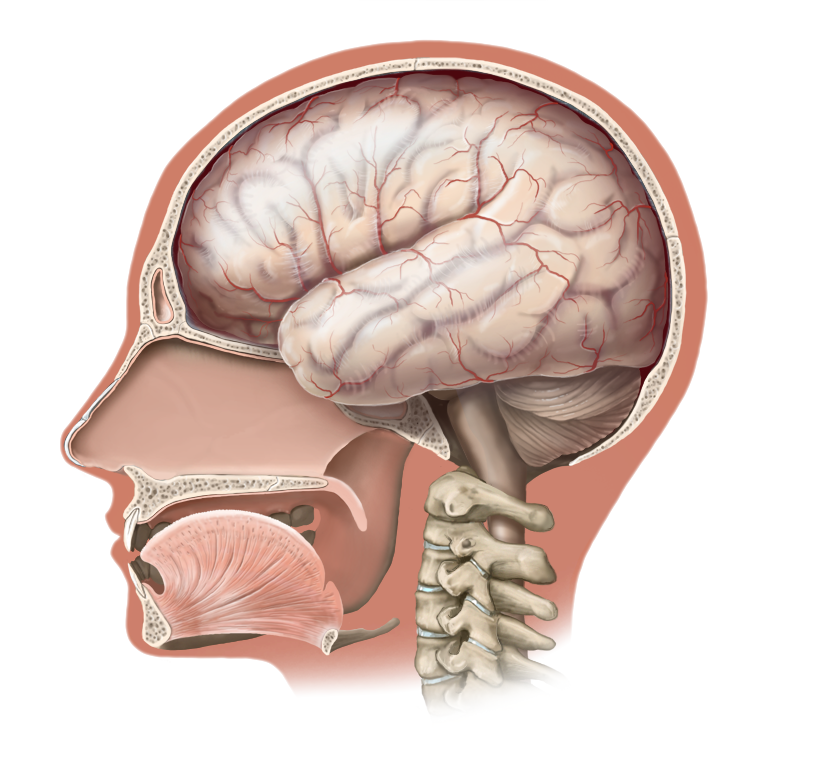

Medical Illustration

All images are works made for hire and are the exclusive property of the client. These are shown as sample purposes of my work only. For licensable work, please see my Illustration Services page.

Medical Illustrator for Precision Graphics, Lachina, and Human Kinetics Publishing (current)

Contract freelancer for many others, some examples of my work below.